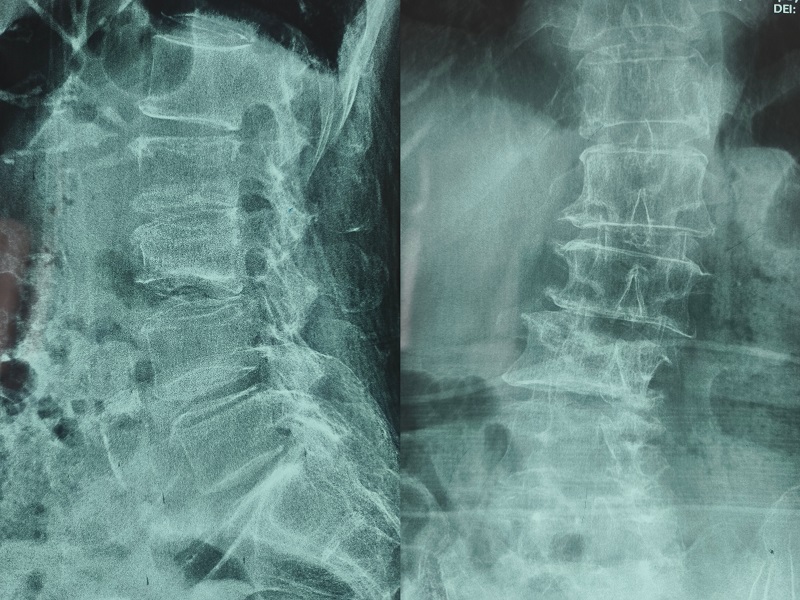

術前圖像